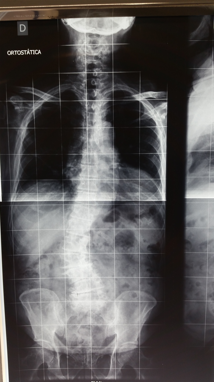

Nos dois planos, fronta e sagital, a linha de prumo deve passar pelo centro da cabeça e da bacia.

Linha de prumo normal da coluna, observe que esta linha deve passar próximo da borda posterior de S1.

Observe este paciente com Escoliose Degenerativa com Flat/Back.

Ele apresente alteração do prumo tanto no plano sagital quanto no coronal decorrente de perda de altura discal e retificação da lordose lombar. Esta deformidade, comum em pacientes idosos, é grave e leva a perda na qualidade de vida e incapacidade funcional, por dor e fadiga muscular.

Neste exemplo o paciente apresenta importante deformidade no plano sagital com escoliose degenerativa compensada no plano coronal. A correção feita objetivou a correção das duas deformidades (plano sagital e coronal) e descompressão posterior.